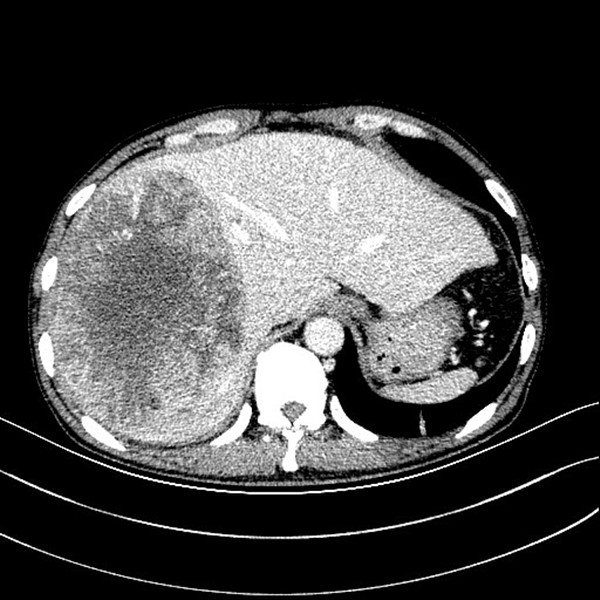

入院后积极完善相关检查,巨大的肿瘤几乎占据整个右半肝,同时伴有肝功异常,少量腹水,考虑肿瘤破裂出血可能。面对如此巨大的肿瘤,经我院肝癌MDT团队评估,认为:“患者门静脉主干和肝右静脉癌栓存在,肝癌射频治疗和介入治疗效果差,手术可能是延长患者生存期的唯一希望”。面对患者绝望而又无助的眼神,家人茫然痛苦的神情,陆宏伟教授及其团队思虑再三,患者存在门静脉右支和右肝静脉癌栓,系介入栓塞治疗禁忌症;巨大肝癌伴陈旧性出血,射频治疗已无意义;靶向药物索拉非尼治疗对一般农民家庭更是奢望;而外科手术切除是给患者延长生命的唯一希望,虽然手术难度巨大,但是一名外科医生不仅要有审时度势的胆识更要有知难而进的担当。

借助普外科3D辅助成像系统术前进行精准评估,实际肝体积3631ml,标准肝体积1288ml,肿瘤体积2048ml,左半肝体积(含尾状叶左半部分)1478ml,除右半肝剩余肝脏体积比标准肝体积大,说明患者左半肝已明显代偿,手术切除是可行的。术前肝功能Child-Pugh A级,ICG 15min滞留率 10.5%,无手术禁忌。